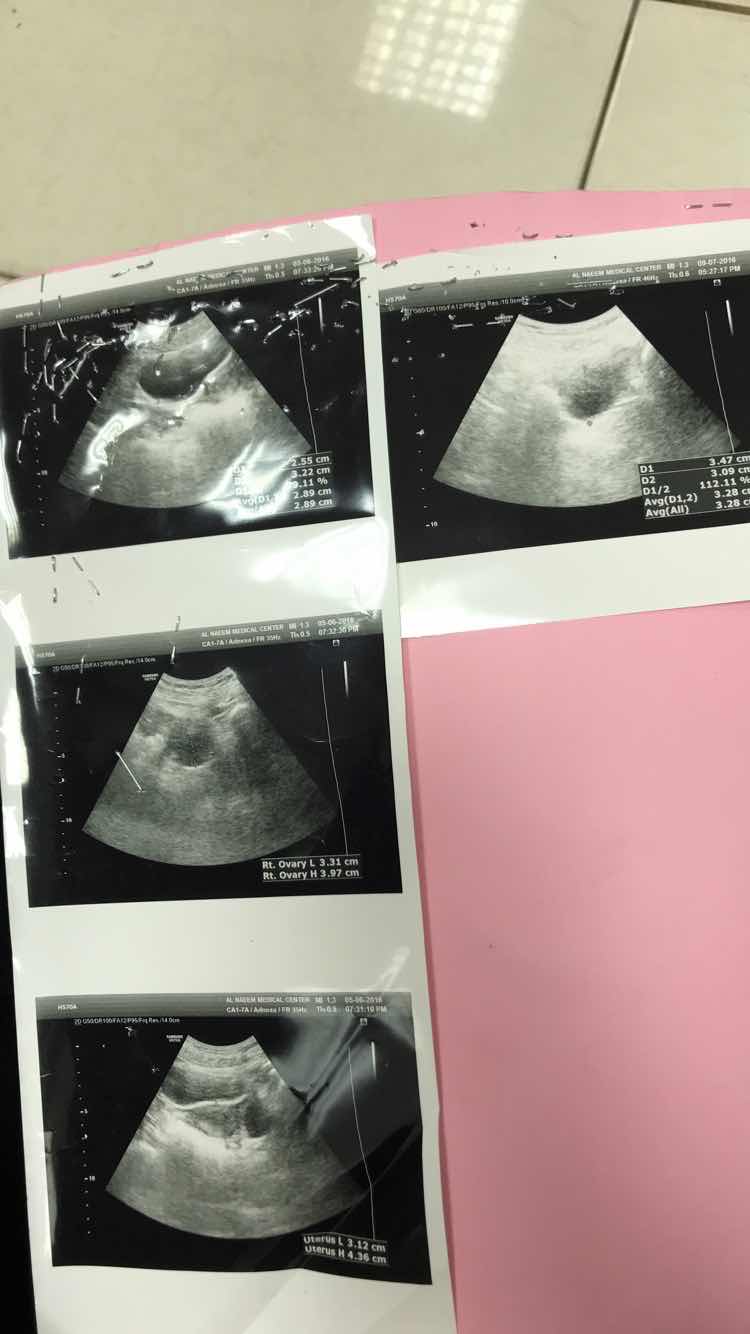

لدي تساقط شديد في الشعر علماً اني اعاني من تكيسات في المبايض هل هي السبب؟